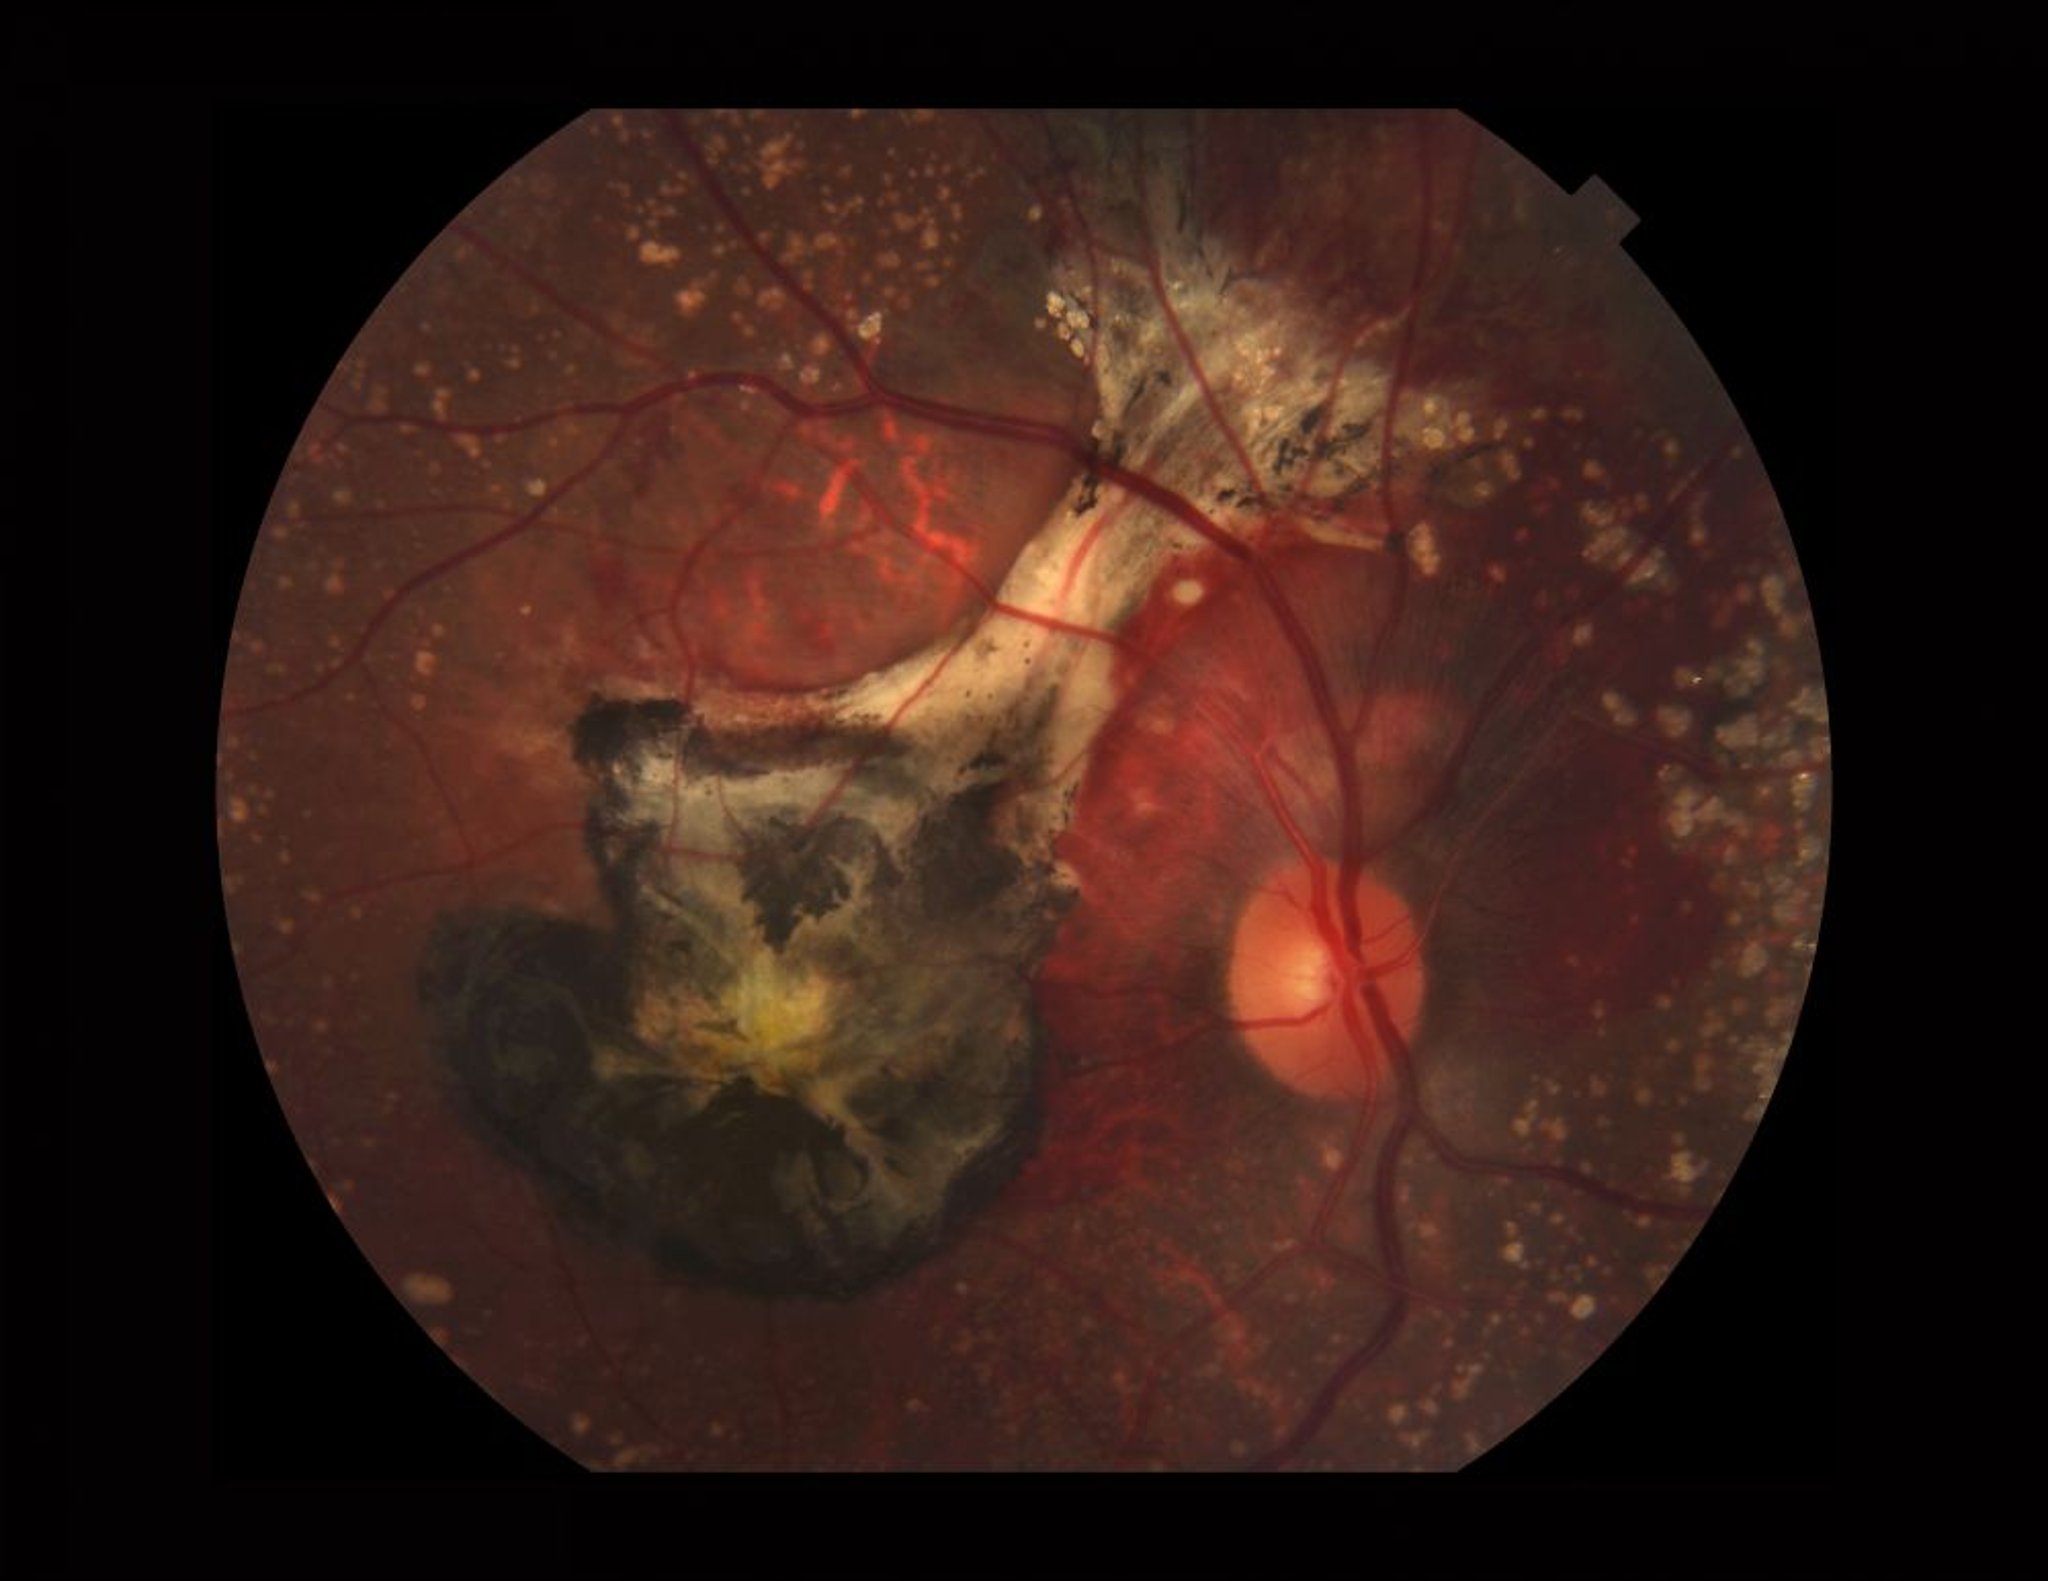

Dégénérescence maculaire liée à l'âge (humide)

Photographie d'une rétine présentant une DMLA humide. Cette image montre des drusen calcifiés, des saignements sous-rétiniens, une membrane néovasculaire choroïdienne (noir dû au sang ancien et à une fibrose), et un pigment xanthophylle (jaune) dans la macula.

PAUL WHITTEN/SCIENCE PHOTO LIBRARY